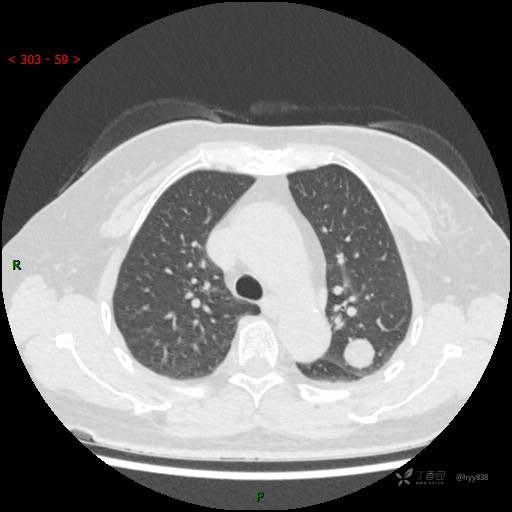

胸部CT平扫